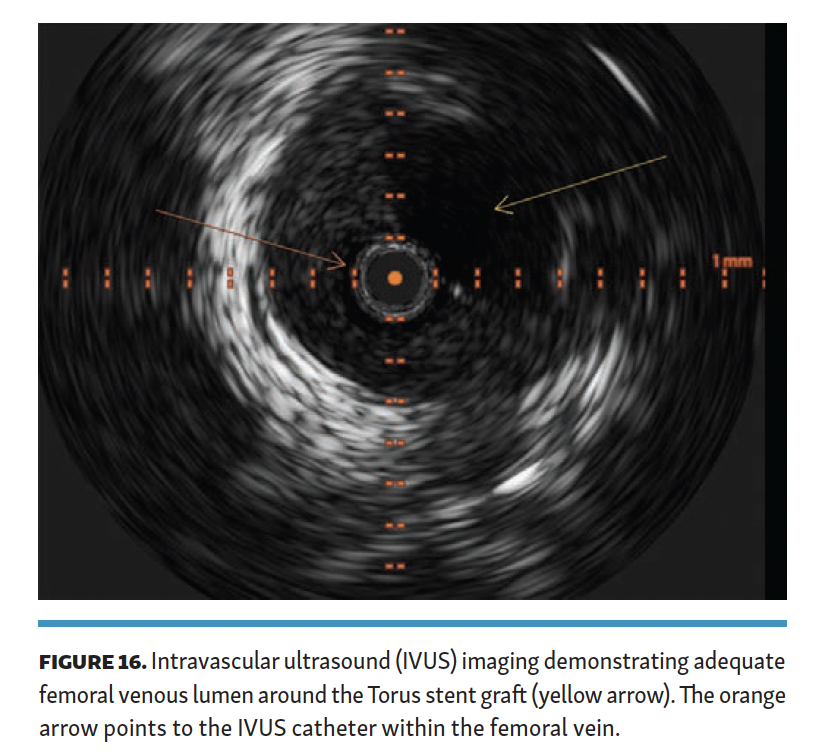

The arteriovenous connection was then ballooned, and the Endocross device was advanced into the femoral vein. Distal angiogram demonstrated multiple areas of occlusion in the distal SFA with the stent in the occluded vein bypass graft entering the proximal popliteal artery (Figure 11). Re-entry into the popliteal artery was obtained below this segment. Following dilation of the retry site (Figure 12), the Torus stent grafts were deployed distal to proximal. Completion angiogram after angioplasty of the stent graft demonstrated brisk flow proximally and into the popliteal artery (Figures 13 and 14). Venogram demonstrated unhindered flow through the femoral vein (Figure 15), and intravascular ultrasound imaging of the femoral vein demonstrated an adequate venous lumen next to the intravenous Torus stent graft (Figure 16). The patient was discharged the following day on 20 mg of rivaroxaban and 81 mg of aspirin once a day. Fluoroscopy of the proximal end demonstrated the Torus stent behind the prior SFA stent and the occluded stent in the proximal portion of the vein bypass graft (Figure 17). Procedural time was 139 minutes, fluoroscopy time 39 minutes, total contrast volume 100 mL, AK 332 mGy, and DAP 5550 µGym2.